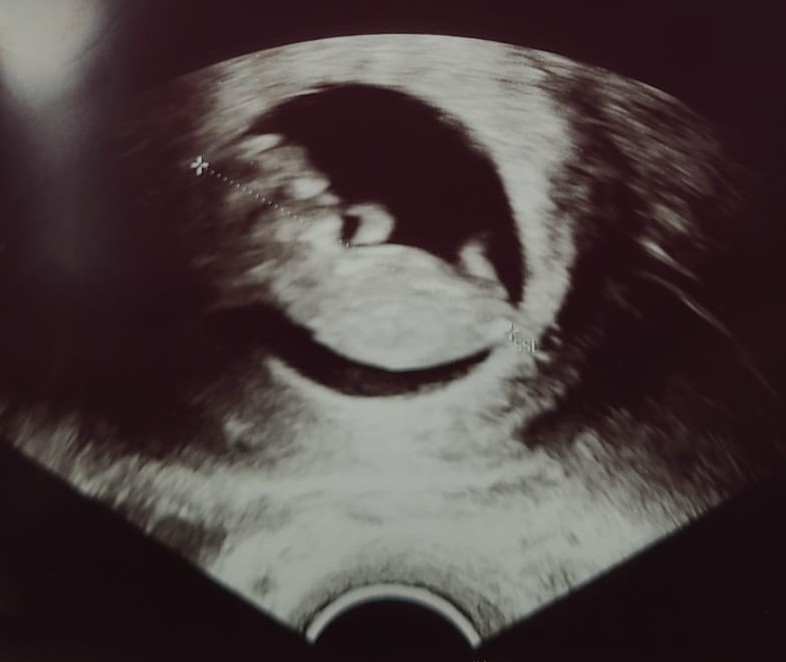

- Images of your baby appear on the screen, and you will be able to see your baby for the first time

- Various measurements are taken, including the crown-rump length and nuchal translucency

This is the most important measurement for dating your pregnancy. The sonographer measures from the top of your baby's head to their bottom. At 12 weeks, this measurement is typically around 5-6 centimetres.

The sonographer will check that your baby's heart is beating normally. At 12 weeks, the heart rate is typically between 120-180 beats per minute.